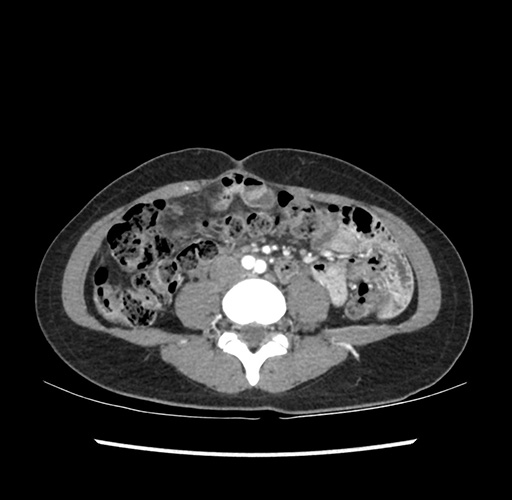

Imaging Analysis

Look through the patient's CT scan to identify any areas of concern for the necessary procedure.

Based on your CT findings, which issue(s) would give reason for "planned slowing down moment(s)" in this case?

Considering a standard left lateral sectionectomy procedure, what step(s) of the operation would you do differently in this case ?